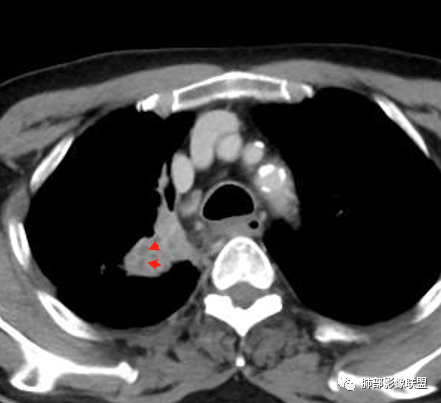

老年男性,病史2年,加重3天

提示慢性病史

加重3天——提示有急性病变,或原病变突然加重

右上胸廓较对侧慢性缩小

右上叶体积缩小

慢性病变有

内部支气管近端狭窄,远端粘液栓

结核要考虑下

内部血管也通畅

边缘也算平直

不踏实的是这里稍膨隆

恶性待排吧